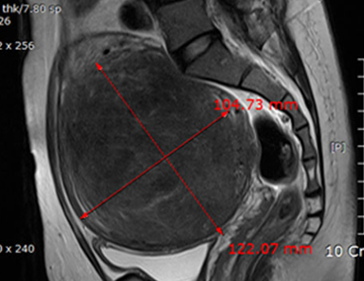

• 시술 전

시술 후